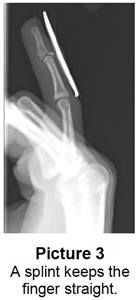

- Splint or cast: Your child may need to wear a splint or cast to keep their finger straight and in one position (Picture 3). For splints, your child:

- Needs to wear it for 24 hours a day for 6 to 8 weeks, even when bathing.

- May need to wear the splint longer than 2 months or at night.

- May take the splint off briefly after bathing, to dry the finger, but the fingertip must always stay straight